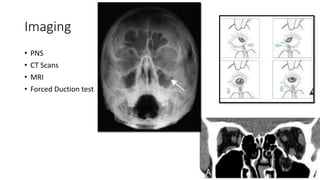

Imaging

• PNS

• CT Scans

• MRI

• Forced Duction test